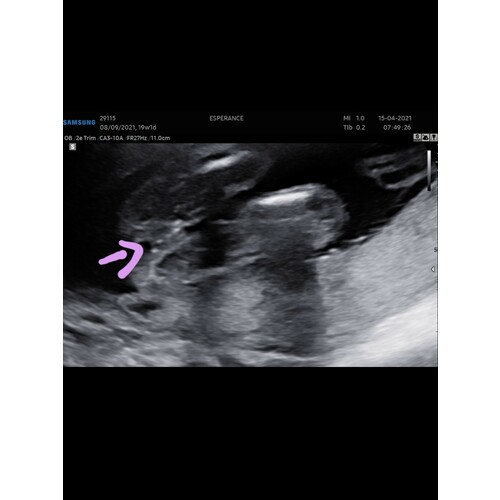

Wij kregen deze foto mee... kan er zelf niet veel van maken, maar de echoscopiste was vrij zeker van haar zaak... we zullen bij 20 weken wel horen of ze gelijk heeft😅

Met 14 weken!

Ziet er zeker uit als een jongen haha. Je ziet duidelijk een piemel en ballen